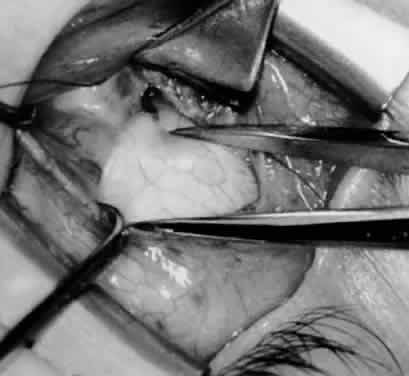

Fig. 1. The standard inferior-temporal fornix incision is made through the conjunctiva and Tenon's capsule with a Westcott scissors. The incision is placed about 8 mm posterior to the limbus, anterior to the fat pad.

Fig. 2. After the lateral rectus muscle is hooked with a Stevens and then a Green muscle hook, the lateral rectus muscle is tented to allow placement of a 4-0 silk suture beneath the insertion of the lateral rectus muscle. The needle tip should glide along the inferior surface of the muscle hook to avoid laceration of the lateral rectus muscle or laceration or penetration of the globe.

Fig. 3. The eye is retracted superonasally with the 4-0 silk traction suture. The suture is attached to the drapes with a hemostat. A Stevens hook is placed along the inferior border of the lateral rectus muscle and drawn temporally. A von Graefe hook is placed within the incision and drawn inferotemporally to expose the inferior oblique muscle.

Fig. 4. A stiff iris repositor can be placed against the sclera to depress the sclera and enhance the view of the inferior oblique muscle. The inferior temporal vortex vein adjacent to the Stevens hook is retracting tissue along the inferior border of the lateral rectus muscle. The second Stevens hook is pointing to the inferior oblique muscle.